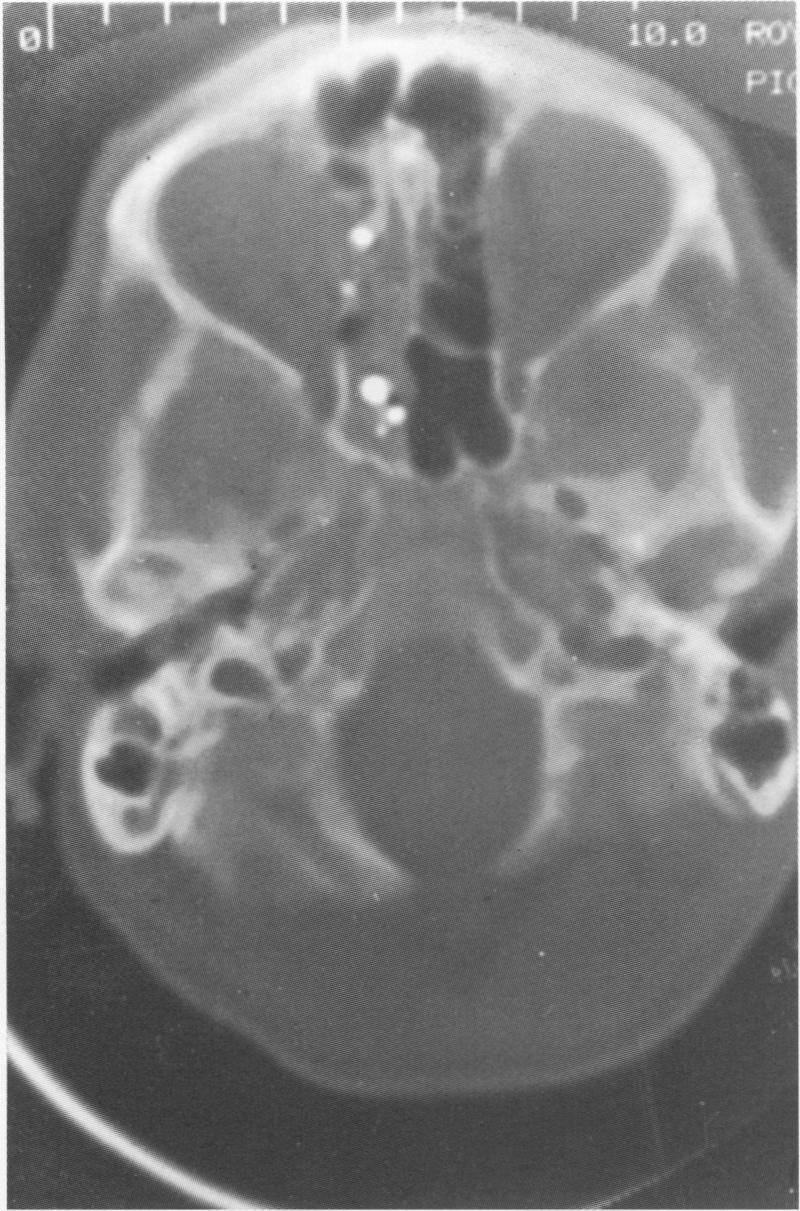

Five cases of fatal airgun injury were identified by forensic pathologists and histopathologists. The circumstances surrounding the case, radiological examination, and pathological findings are described. The weapon characteristics are also reported.

Three of the victims were adult men, one was a 16 year old boy, and one an eight year old child. Four of the airguns were .22 air rifles, the other a .177 air rifle. Two committed suicide, one person shooting himself in the head, the other in the chest. In both cases the guns were fired at contact range. Three of the cases were classified as accidents: in two the pellet penetrated into the head and in one the chest.

方法

受害者中3人为成年男性,1人为16岁男孩,1人为8岁儿童。气枪中有4把是.22气步枪,另一把是.177气步枪。2人自杀,一人朝头部开枪,另一人朝胸部开枪。两起案件中枪都是在接触距离发射的。3起案件被归类为意外:2起中弹丸射入头部,1起射入胸部。